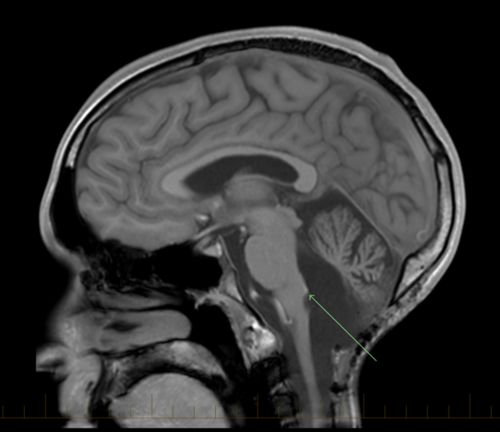

اعراض ورم الدماغ عند الاطفال. ما هي أعراض الورم في الرأس. Brain tumor بنمو كتلة من الخلايا غير الطبيعية في الدماغ ومع ازدياد حجم الورم قد يزداد الضغط داخل الجمجمة سواءا كان هذا الورم حميدا أو سرطانيا وهذا ما قد يتسب ب. تتنوع علامات وأعراض ورم الدماغ عند الأطفال تنوع ا كبير ا وتعتمد على حجم ورم الدماغ وموقعه ومعدل نموه. وبعض العلامات والأعراض لا يمكن اكتشافها بسهولة وذلك لأنها تشبه أعراض حالات أخرى.

وبعض العلامات والأعراض لا يمكن اكتشافها بسهولة وذلك لأنها تشبه أعراض حالات أخرى. تعتبر أورام الدماغ لدى الاطفال اليوم أكثر أنواع الأورام شيوعا بين الأطفال تتسم أورام الدماغ بظهور علامات مثل الضغط العام في الجمجمة ضغط داخل القحف intracranial pressure أو أعراض موضعية من الممكن أن تؤدي لاضطراب عصبي معين. المراجع العدوى التي تصيب الد ماغ نذكر من أمراض العدوى التي ت صيب الد ماغ ما يأتي ١. تتنوع علامات وأعراض ورم الدماغ عند الأطفال تنوع ا كبير ا وتعتمد على حجم ورم الدماغ وموقعه ومعدل نموه.